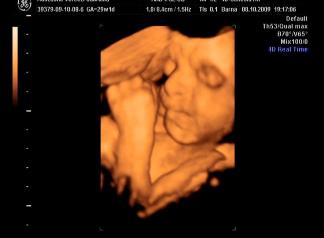

Briell! Nagyon szepek a kepek, a szemtakarosak mindig nagyon cukik, de a labikos sem semmi